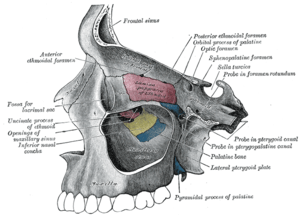

Medial wall of left orbit. Lateral wall of nasal cavity.

Lateral wall of nasal cavity. Sagittal section of nose mouth, pharynx, and larynx.